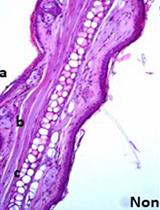

Toxoplasmosis caused by the intracellular parasite Toxoplasma gondii, is characterized by a life-long chronic infection. The parasite is an efficient neurotropic infectious agent that establishes its “safe” life by forming intracellular cysts in chronically infected animals and humans. This protocol describes the specific recipes and method to stain brain cysts from infected mice and rats for further quantification using epifluorescence microscopy. This method provides the possibility to scan the entire brain and thus to numerate all cysts.